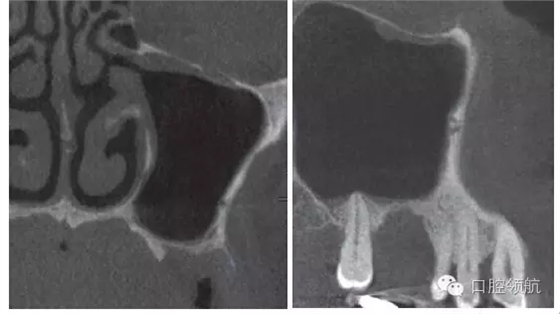

拔除(左上第六顆牙)后,抗生素(500mg)口服1周。術(shù)后4周的CBCT顯示,上頜竇黏膜增厚明顯改善(圖3)。

圖3 拔牙后4周,上頜竇黏膜增厚消失,但仍有殘留牙槽窩。